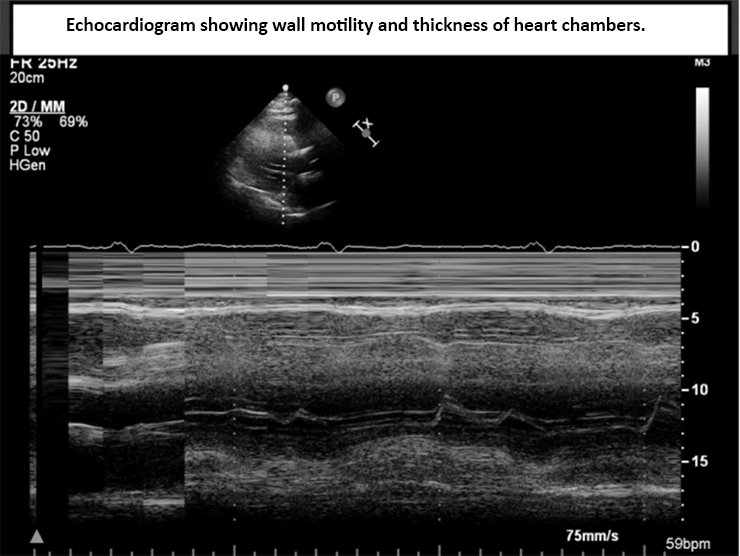

Image B: Echocardiogram showing wall motility and thickness of heart chambers.

To better understand the impact of a bariatric operation and weight loss on heart health, the researchers compared preoperative and postoperative echocardiography readings. An echocardiogram is an ultrasound of the heart that measures not only its size and geometry, but also its function. An echocardiogram measures how much blood is in the heart, how much blood goes out of the heart, and how much blood remains in the heart.